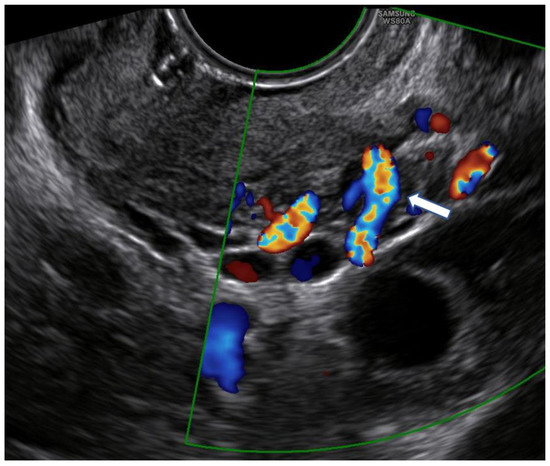

2.2. Pre-Excisional Cervical Examination

2.5. Follow-Up